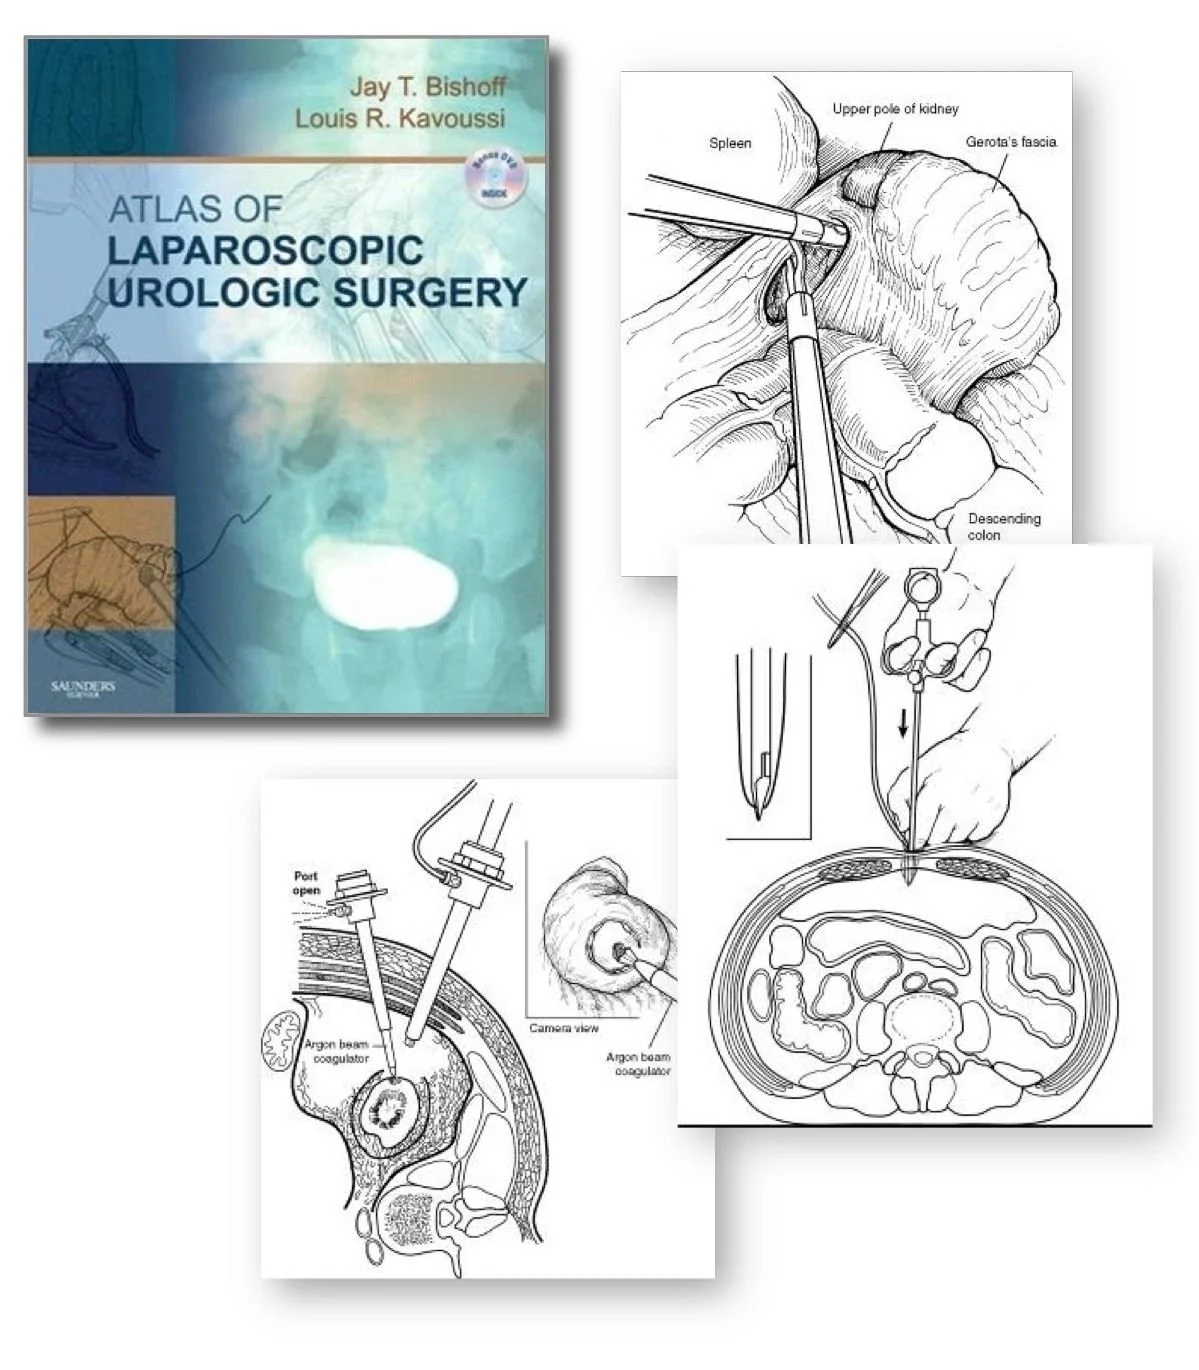

Instructional illustrations are used to teach or explain medical information to a specific target audience. Examples include;

Publications including textbooks and journals.

Surgical illustrations visually depict operative techniques, surgical anatomy, and complex procedures. They are created with high anatomical accuracy and serve as a visual bridge between complex surgical knowledge and learners, clinicians, or patients.

Textbook Illustrations

The Atlas Project